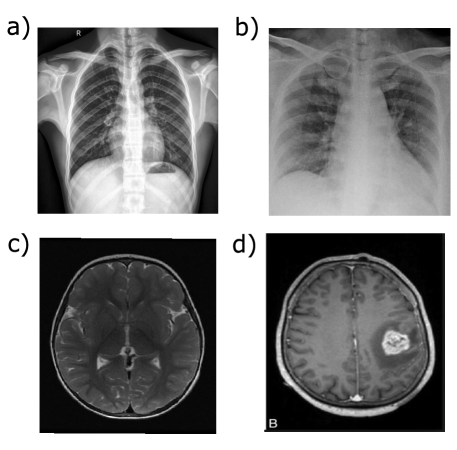

In the present study, we used two types of medical images to evaluate the proposed technique. We used a dataset that includes X-ray images of lungs from patients affected by SARS-CoV-2 (COVID-19) and healthy patients [61]. The dataset includes 227 images. Two categories, were extracted from the image set by implementing a supervised algorithm to identify the classes, as shown in Figure 4(a, b).

We also used a dataset with 253 images. The dataset included magnetic resonance imaging (MRI) images, some displaying brain tumors and some with healthy brain structures [62]. In this case, our aim was to identify abnormalities in the brain structure. Figure 4(c, d) shows both classes, patients with positive and negative diagnoses.